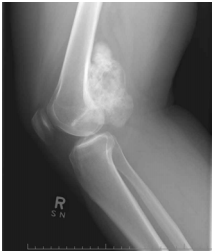

25 某 32 歲女性患者主訴右膝膕腫脹感伴有輕微疼痛已三年,經檢查,被動屈膝至 50 度便受限,觸診 患處,慢慢用力按壓,腫脹處並不會隨著壓力而明顯產生體積變化,經 X 光檢查如圖所示。則下列 何項診斷最有可能?

(A)膕窩囊腫 (B)骨腫瘤 (C)肌肉血腫 (D)類風濕性關節炎